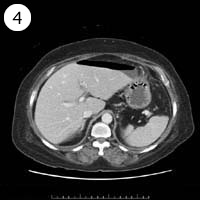

57歳 女性

単純CT

造影CT

※異常画像を赤枠で示しています